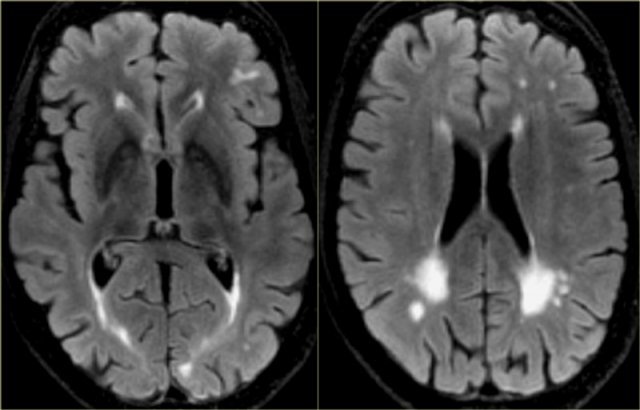

Pin On B R A I N I M A G E S

www.pinterest.com

www.pinterest.com

brain matter mri white disease imaging dementia alzheimer scan vascular hyperintensities normal magnetic resonance alzheimers hyperintensity t2 google intensities bmj

Vascular Dementia | Radiology Reference Article | Radiopaedia.org

radiopaedia.org

radiopaedia.org

Dementia, MRI Scans - Stock Image - M140/0435 - Science Photo Library